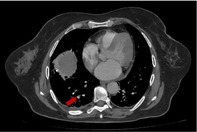

Lemierre syndrome (LS) is a rapidly progressing disease characterised by a recent oropharyngeal infection, complicated by septic emboli and thrombophlebitis of the internal jugular vein (IJV). We describe a case of a 65-year-old woman who presented to the emergency room with a 14-day history of progressive occipital headache, fever and odynophagia. Radiological investigations showed bilateral IJV thrombophlebitis, multiple cavitated pulmonary nodules suggestive of septic emboli and a subsegmental pulmonary arterial thromboembolism. A diagnosis of LS was made. The patient received antibiotic treatment with intravenous ceftriaxone and clindamycin for 2 weeks, followed by 4 weeks of oral clindamycin at home and anticoagulation with enoxaparin followed by warfarin. One-month follow-up imaging revealed complete resolution of IJV thrombosis and pulmonary findings. This case displayed the rarely reported association of pulmonary arterial thromboembolism and pulmonary septic emboli.

Abstract Image